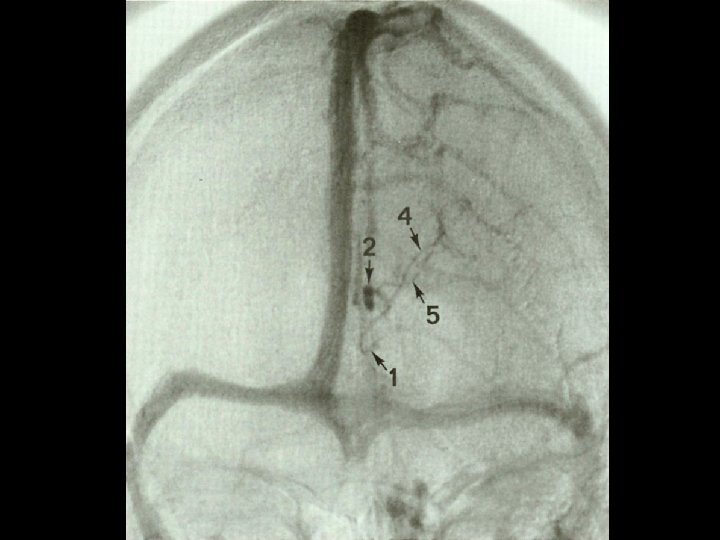

Dural Sinuses • Sagittal sinuses – superior and inferior • Cavernous sinus • Petrosal sinuses – superior and inferior • Occipital sinus • Straight sinus • Transverse sinus • Sigmoid sinus Michigan Neurosurgery

Deep Veins Michigan Neurosurgery